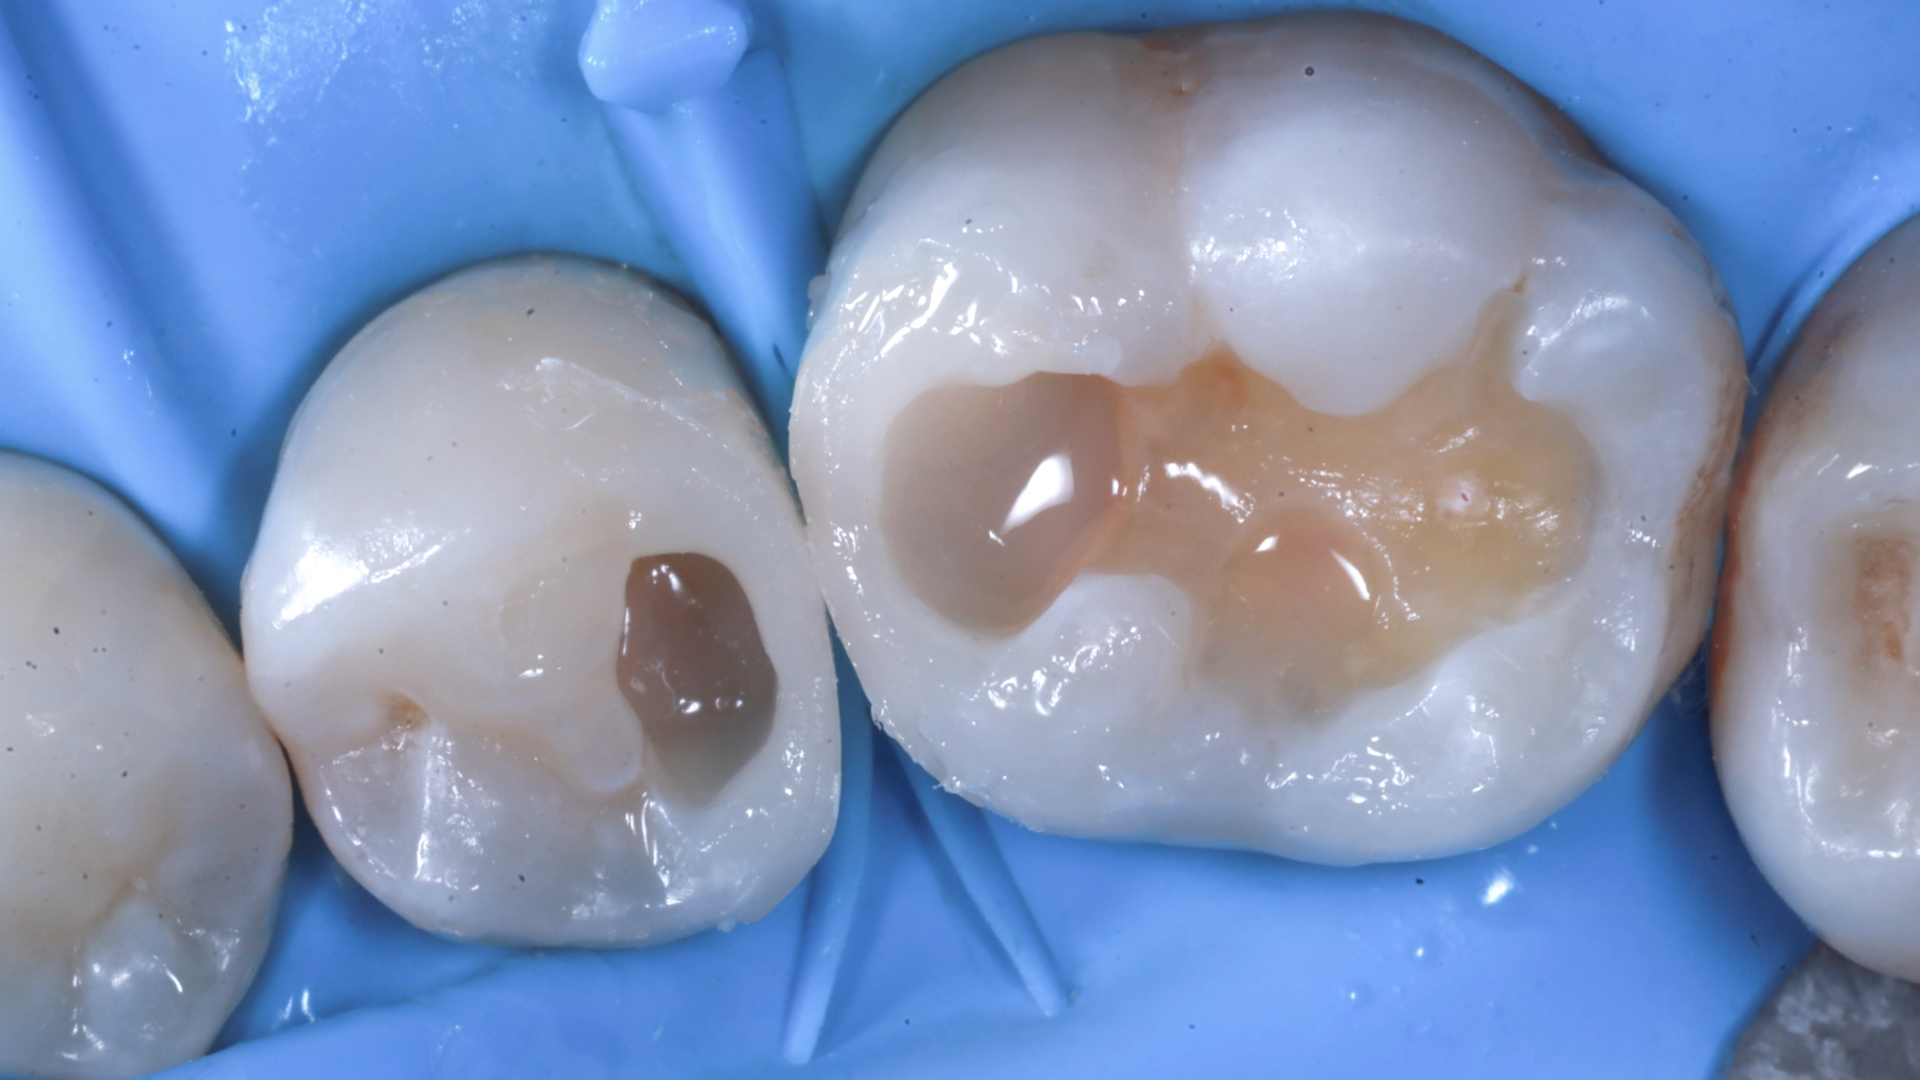

Verifica fotografica del sigillo cervicale distale a 2.5 Creazione della parete inter-prossimale distale a 2.5, eliminazione della matrice e successivo inserimento del cuneo d dell’apposito anello con una sola attrice mantenuta

Creazione della parete mesiale a 2.6 Applicazione di flow con caratteristiche bulk per minimizzare sul fondo cavitario

Modellazione della superficie occlusale ed intensificazione dei solchi con pigmento “brown” Modellazione occlusale da un aspetto vestibolare